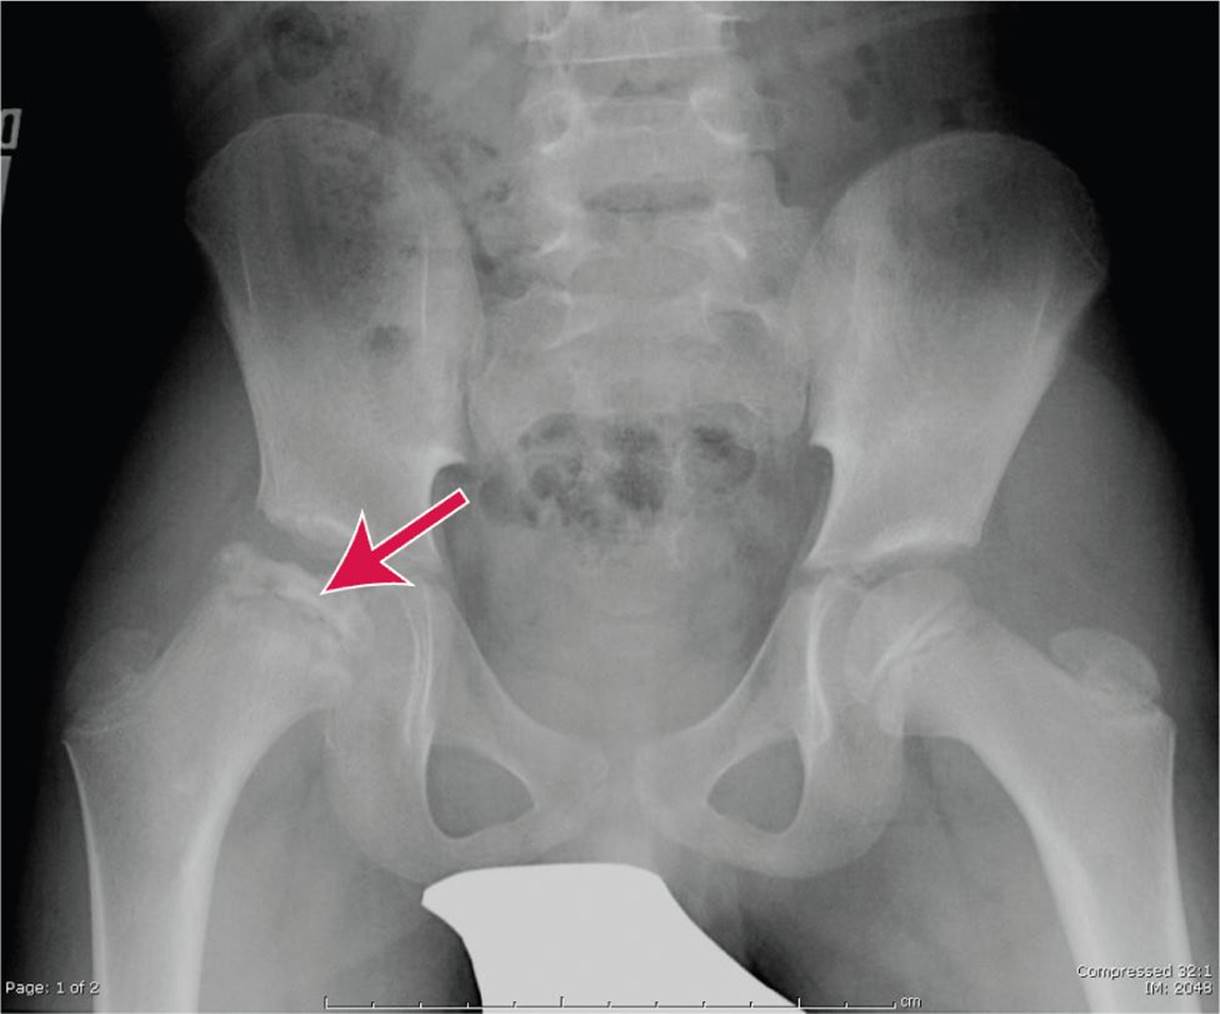

Consider avascular necrosis of the femoral head in patients with hip pain (see Fig. 86-1).

FIG. 86-1. Avascular necrosis of the femoral head. (Courtesy of Hollie Jackson, MD.)